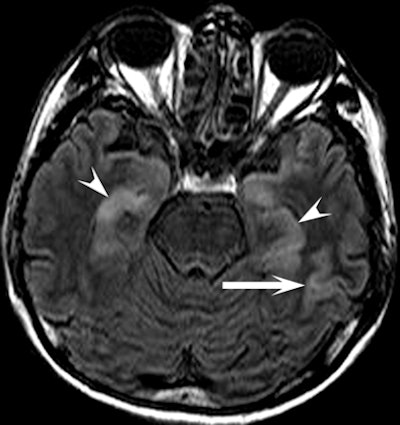

| Clinical images of a 51-year-old man found unconscious with a Glasgow Coma Scale score of 7 and withdrawal to pain. Above image shows fluid-attenuated inversion recovery, while below is a diffusion-weighted image that shows an increase in signal intensity in the head, body, and tail of the hippocampus bilaterally (arrowheads) and in the cerebral cortex (arrow). All images courtesy of Radiology and the National Neuroscience Institute. |

In a review of the images, the researchers found the hippocampus was affected bilaterally in seven patients, with variable involvement of the cortex in the parietal lobe (seven patients), temporal lobe (six patients), occipital lobe (five patients), and frontal lobe (five patients).

In seven patients, there was cortical involvement that the authors described as "patchy noncontiguous" in four cases and "confluent" in three patients, with sparing of the subcortical white matter and cerebellum. Three patients displayed abnormalities of the splenium of the corpus callosum in addition to the cortex.

"These findings are consistent with those of previous studies that described selective vulnerability of the brain to hypoglycemic damage and characteristic lesion distribution," the authors wrote.